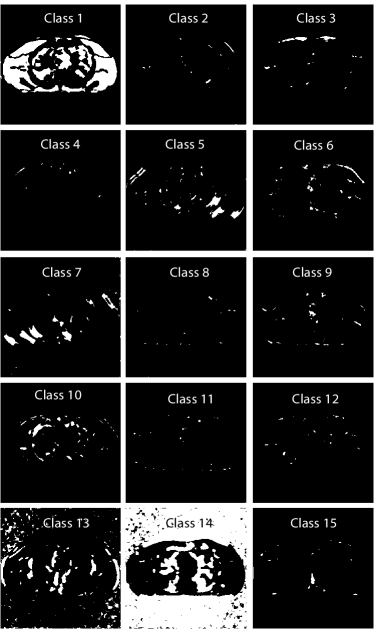

We compare the RMSE and the SSIM for SPULTRA with those for PWLS-EP and PWLS-ULTRA. Tab. II lists the two metrics for the reconstruction targeted ROI after sufficient iterations (800 iterations) for convergence of PWLS-EP, PWLS-ULTRA, and SPULTRA, for various dose levels. The results show that SPULTRA achieves significant improvements in RMSE and SSIM in low-dose situations. Notably, compared to PWLS-ULTRA, SPULTRA further decreases the RMSE by up to 1.3 HU when , and by around 3.3 HU when .

The RMSE improvement of SPULTRA over PWLS-ULTRA can be more clearly observed from Fig. 3 that shows the RMSE evolution with the number of outer iterations under different dose levels. At low-doses, SPULTRA decreases the RMSE more quickly (from the same initial value) and to much lower levels than PWLS-ULTRA. Fig. 3 shows that to achieve the same RMSE as PWLS-ULTRA at 600 outer iterations, SPULTRA takes 487, 365, 251 and 133 outer iterations under , respectively.

V-A4 Computational Costs

As discussed in Sec. III-D, SPULTRA has a similar computational cost per iteration as PWLS-ULTRA, except for computing some initializations for image update. Fig. 3 shows that the SPULTRA method requires much fewer number of outer iterations than PWLS-ULTRA to achieve the same RMSE for the reconstruction, especially at low doses.

When the dose is very low, e.g., when , SPULTRA takes only a quarter the number of outer iterations as PWLS-ULTRA to achieve the same RMSE. Thus, the total runtime to achieve a specific reconstruction quality at low doses is typically much lower for SPULTRA than for PWLS-ULTRA. When the dose is not very low, for example when , the SPULTRA and the PWLS-ULTRA methods have similar computational costs and runtimes. To achieve RMSE of 29.26 HU (see Fig. 3(a)), PWLS-ULTRA requires 600 outer iterations, while SPULTRA requires 487 584 effective outer iterations where the additional runtime is associated with initializations in each SPULTRA outer iteration.

V-A5 Visual Results and Image Profiles

Fig. 4 shows the reconstructed images and the corresponding error images for PWLS-EP, PWLS-ULTRA, and SPULTRA, at and . Compared to the PWLS-EP result, both PWLS-ULTRA and SPULTRA achieved significant improvements in image quality in terms of sharper reconstructions of anatomical structures such as bones and soft tissues, and suppressing the noise. However, the PWLS-ULTRA method introduces bias in the reconstructions, which leads to larger reconstruction errors compared to the proposed SPULTRA method. In Fig. 4, we marked three 3D ROIs in the axial plane, i.e., ROI 1, ROI 2, and ROI 3. Fig. 5 shows the zoom-in images of a 3D plot of ROI 1, and those of ROI 2 and ROI 3 are shown in the supplement. We also plot the evolution of RMSE through the axial slices of the three 3D ROIs in Fig. 6. The figures demonstrate that SPULTRA clearly outperforms the competing PWLS-EP and PWLS-ULTRA schemes.

The above advantages of SPULTRA can be seen more clearly when observing the image profiles. Fig. 7 plots the image profiles for the three methods together with that of the ground-truth image. Fig. 4 shows the horizontal green solid line and the vertical red dashed line, whose intensities are plotted in Fig. 7. It is obvious that the profiles for SPULTRA are closest to the ground-truth among the three compared methods. The gap between the profiles of the PWLS-based methods and the ground-truth shows the bias caused by the compared PWLS methods.